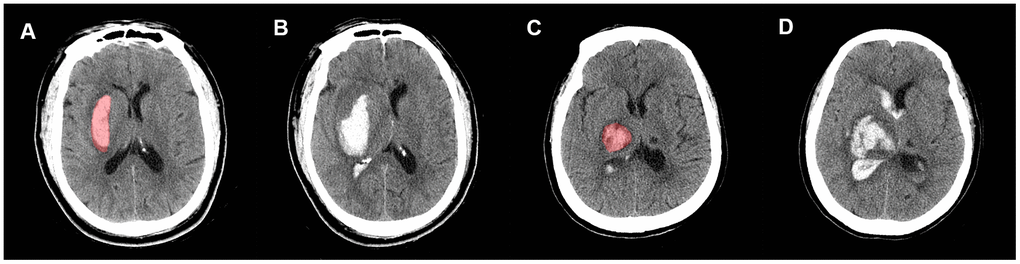

New IVH refers to patients who had no baseline IVH but developed a new IVH lesion in follow-up CT images (<72 h) (Figure 5A, 5B). IVH expansion was defined as an absolute increase from the baseline IVH volume of >2 mL between the initial and follow-up CT images (Figure 5C, 5D). We chose a threshold of 2 mL to define IVH expansion because it is correlated with poor outcome and mortality [32]. IVH growth includes new and expanding IVH. We restricted hematoma to the deep brain region for several reasons. First, deep ICH locations are more likely to have HE [35]. Second, hematomas in the deep region (thalamus and basal ganglia) are closer to ventricle systems and have a higher risk of IVH growth and poor outcome [36, 37]. Third, in this exploratory study, we tried to exclude as many confounders as possible. Thus, we decided to exclude the non-deep hematomas and focus on the hematomas that had a greater risk for IVH growth (deep hematomas).

Figure 5. Representative illustration of new IVH, IVH expansion, and manual region of interest (ROI) segmentation. Images (A, B) are non-contrast CT images (axial view) of a 54-year-old male who experienced a new IVH. There was no baseline IVH (A), but the hematoma broke into ventricles on the follow-up CT (B). Images (C, D) are non-contrast CT images (axial view) of a 68-year-old female who experienced IVH expansion; (C) shows an initial IVH with a volume of 2.53 mL; follow-up CT (D) shows that the volume of IVH increased to 22.31 mL within 72 h.